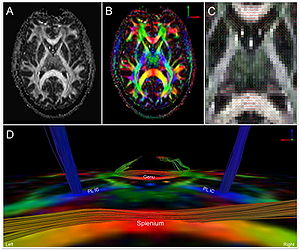

|

Publication: PLoS One. 2015 Oct 7;10(10):e0139434. PMID: 26444010 | PDF Authors: Tax CM, Chamberland M, van Stralen M, Viergever MA, Whittingstall K, Fortin D, Descoteaux M, Leemans A. Institution: Image Sciences Institute, University Medical Center Utrecht, Utrecht, The Netherlands. Background/Purpose: Fiber tractography plays an important role in exploring the architectural organization of fiber trajectories, both in fundamental neuroscience and in clinical applications. With the advent of diffusion MRI (dMRI) approaches that can also model "crossing fibers", the complexity of the fiber network as reconstructed with tractography has increased tremendously. Many pathways interdigitate and overlap, which hampers an unequivocal 3D visualization of the network and impedes an efficient study of its organization. We propose a novel fiber tractography visualization approach that interactively and selectively adapts the transparency rendering of fiber trajectories as a function of their orientation to enhance the visibility of the spatial context. More specifically, pathways that are oriented (locally or globally) along a user-specified opacity axis can be made more transparent or opaque. This substantially improves the 3D visualization of the fiber network and the exploration of tissue configurations that would otherwise be largely covered by other pathways. We present examples of fiber bundle extraction and neurosurgical planning cases where the added benefit of our new visualization scheme is demonstrated over conventional fiber visualization approaches. Funding:

|